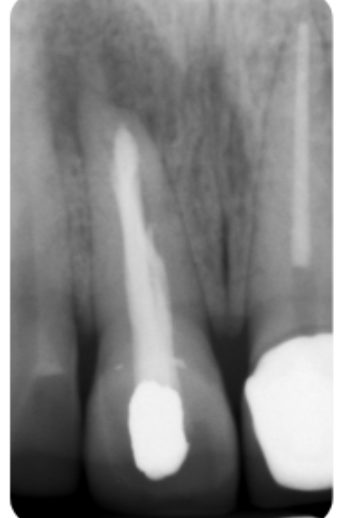

Following endodontic treatment, the root filling should be cut to below the level of the gingival margin to prevent this problem occurring (Figure 5). The pulp chamber can be cleaned using ultrasonics and alcohol to remove fine traces of sealer.

- Removal of the coronal gutta percha to 3-4mm below the level of the cemento-enamel junction (CEJ) or gingivo-epithelial attachment. A heated plugger, gates-glidden or thin gooseneck burs are useful for cutting back the GP. A periodontal probe or Machtou plugger can be used to check the depth is sufficient

- Place a 2-3mm barrier (subseal) over the GP. This will prevent bacteria or hydrogen peroxide from penetrating the root filling. Various materials have been suggested for this including IRM, GIC and composite. I prefer IRM because it is easy to handle. It also has a white colour and can be easily removed from the dentine walls. GIC or composite (especially the bonding agent) can sometimes remain on the canal wall and prevent the bleaching agent from penetrating the dentinal tubules